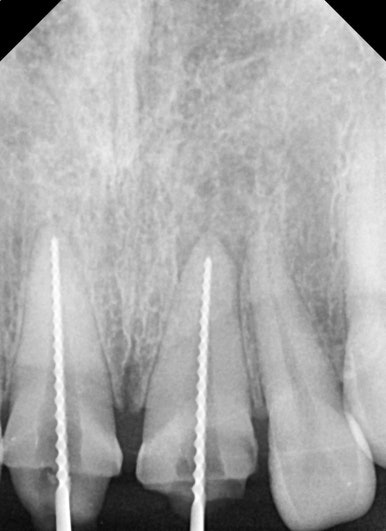

엑스레이 검사 결과, 뿌리 끝에는 염증도 생겨 있었습니다.

단순히 겉모습의 문제만이 아니라, 치아 뿌리 쪽도 치료가 필요했던 상황이었습니다.

치료는 재신경치료와 BOPT컨셉을 이용한 크라운 재치료로 계획했습니다.